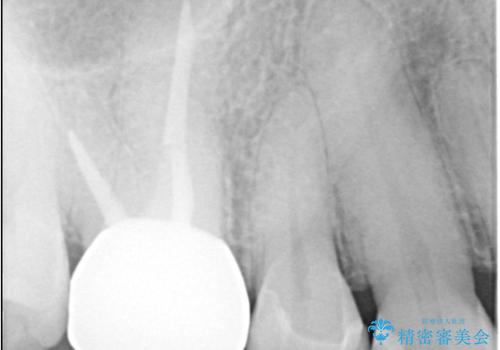

- 定期検診にてむし歯が見つかった患者さまです。

金属アレルギー体質とのことで、セラミックインレーにて修復治療を希望されました。

セラミックインレーは、金属やプラスチックに比べ汚れが着きづらく、むし歯の再発リスクを減らすことができます。